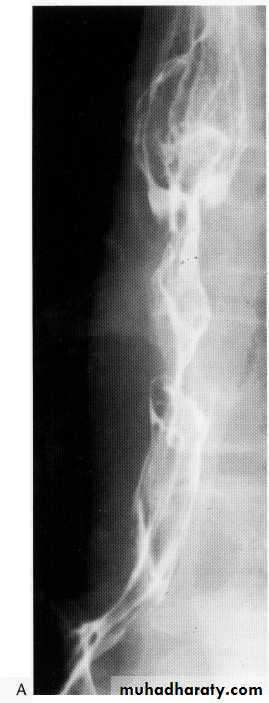

Tertiary contractions